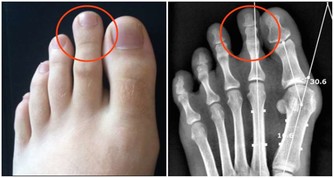

第三類:骨質疏鬆導致腰痛

中老年女性,特別是絕經後的女性,由於脊柱的骨量減少,脊柱承重能力隨之降低,機體在負重甚至行走中也會出現腰背部疼痛。

50%以上的骨質疏鬆患者會出現疼痛的症狀,且腰椎和髖部都是最早發生骨質疏鬆的部位,所以很多骨質疏鬆的患者,在患病初期都會腰痛的症狀。